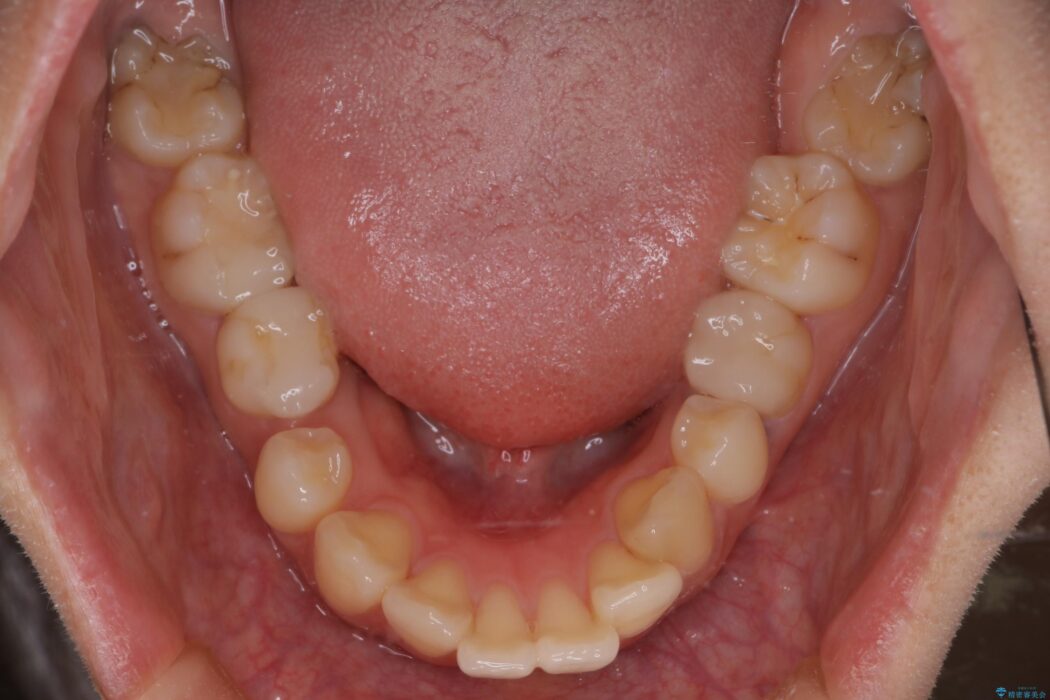

口元が出ていることを気にされ、ご来院された患者様です。

精密検査の結果、前歯を大きく後退させ、口元の突出感を改善するためには、スペースの確保が必要と診断しました。

そこで、上下左右の第一小臼歯(4番目の歯)を計4本抜歯し、そのスペースを利用して前歯全体を奥へ移動させる抜歯矯正の治療計画を立案。